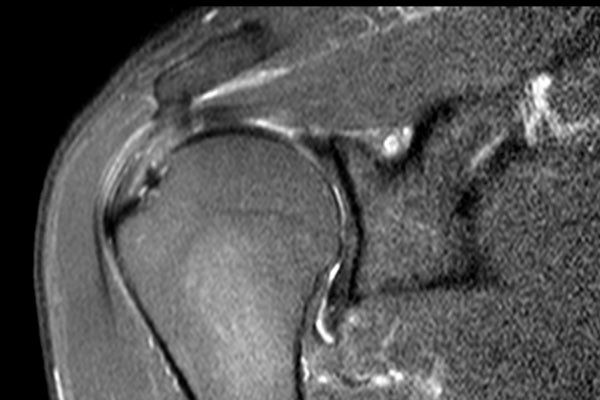

Có hình ảnh rách toàn bộ chiều dày phần trước của gân cơ trên gai, kéo dài từ mặt khớp đến mặt túi hoạt dịch.

Do các sợi gân phía sau của gân cơ trên gai còn nguyên vẹn, tổn thương này được gọi là rách toàn bộ chiều dày không hoàn toàn của gân cơ trên gai.

Không có co rút.